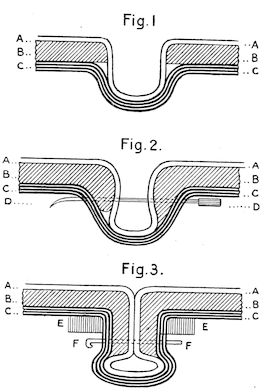

Fig. 2.—Horse suffering from osseous cachexia.

Fig. 3.—Pig suffering from osseous cachexia (fourth stage).

Fig. 4.—Deformity of the face in the horse shown in Fig. 2.

Fig. 5.—Head of a pig suffering from osseous cachexia.

Fig. 6.—Osseous cachexia. This condition developed in two months, the last month of gestation and the first of lactation.

Fig. 7.—Osseous cachexia: softening of the maxillæ.

Fig. 8.—Transverse section through the middle region of the face in a pig suffering from osseous cachexia.